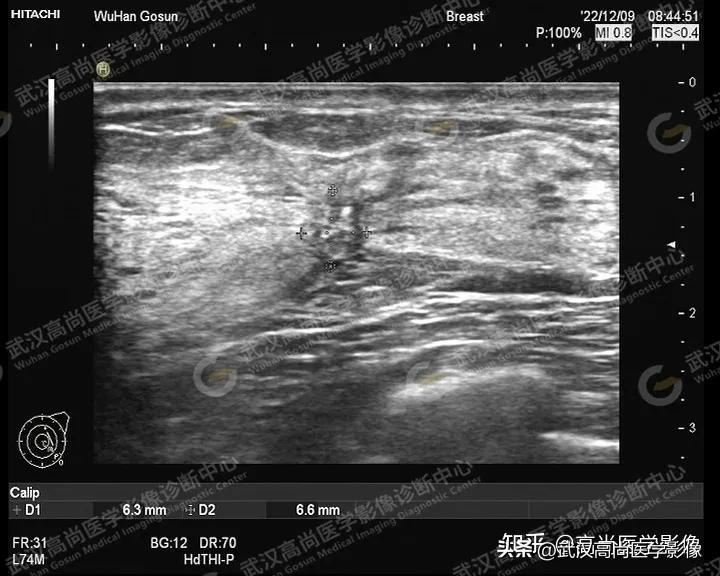

病例三:

女,41岁,自述外院彩超检查怀疑乳腺癌,来本中心进一步检查,无不适。

超声影像如下:

图一:左侧乳腺见1-2点方向见一形态不规则,边界模糊,非平行方位生长的低回声区,周围组织可见扭曲,并可见多处小无回声,范围约6.3x6.6mm。